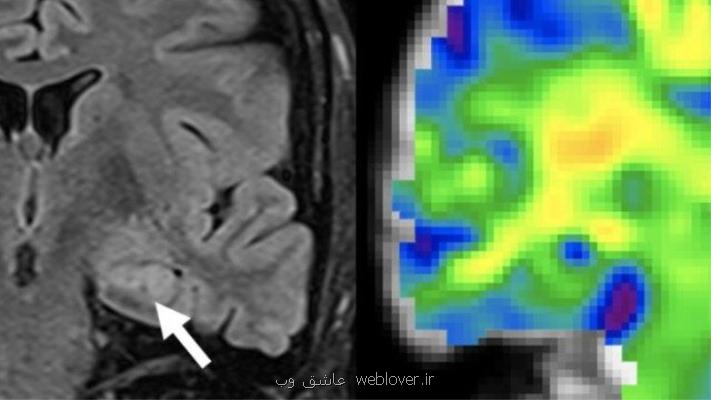

“گراهام هیوزمن”(Graham Huesmann) متخصص مغز و اعصاب موسسه بکمن اظهار داشت: تغییرات ساختاری مغز، در پاسخ به تشنج، موجب مرگ سلول های عصبی و تشکیل بافت اسکار می شود. زمانی که شاهد تغییراتی در ام.آر.آی هستیم، بیماری بسیار پیشرفته است. ما می خواستیم این مساله را زودتر و با بهره گیری از ارتجاع نگاری یا الاستوگرافی تشدید مغناطیسی تشخیص دهیم. ارتجاع نگاری یا الاستوگرافی تشدید مغناطیسی از اسکنر ام.آر.آی جهت بررسی سفتی بافت های مغز استفاده می نماید.

در این مطالعه پژوهشگران از الاستوگرافی تشدید مغناطیسی برای دیدن تغییراتی در هیپوکامپ استفاده کردند. ارتجاع نگاری یا الاستوگرافی(Elastography) یک روش تصویربرداری پزشکی است که قابلیت ارتجاع و سختی(stiffness) بافت نرم را تعیین می کند. دلیل سنجش نرمی و سختی بافت این است که با بهره گیری از این کار می توان وجود یا وضعیت پیشرفت برخی بیماری ها را تشخیص داد. برای مثال تومورهای سرطانی معمولاً سخت تر از بافت اطراف هستند، مثال دیگر کبدهای بیمار است که نسبت به کبدهای سالم سخت تر هستند.

پژوهشگران گفتند: هیپوکامپ قسمتی از مغز است که در حافظه نقش دارد. در مراحل اولیه صرع، کمی آزار به ساختار وارد شده است که می توانیم با الاستوگرافی تشدید مغناطیسی آنرا تشخیص دهیم.